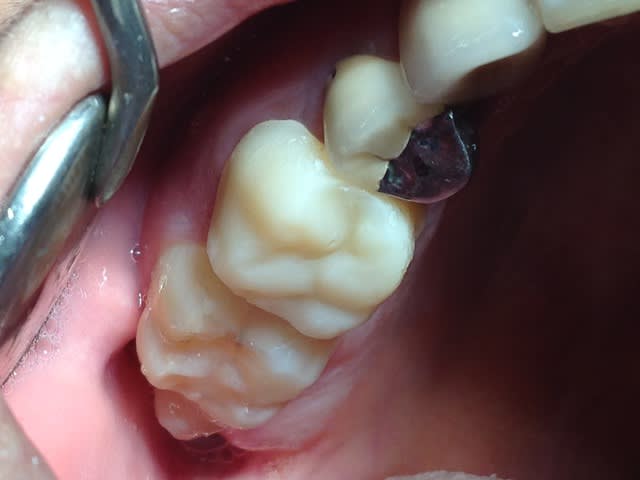

80% du temps, du fuji 2LC (photopolymérisable, avec conditionneur) avec une automatrice (photo 4).

Parfois quand je n'arrive pas à matricer parce que limite trop basse un compo fluide remonté à la main avec mise en place de fil de rétraction dans le sulcus (radios 5 et 6) Mais cela n'est possible que pour un délabrement réduit, une paroi max.

Quand je dépose une couronne/inlay core et que la dent est "à plat", un provisoire (isomoulage) scellé en définitif (fuji plus) après protection au cavit des entrées canalaires. Y a plus qu'à repasser au travers, ça tient très très bien (photos 1,2,3)